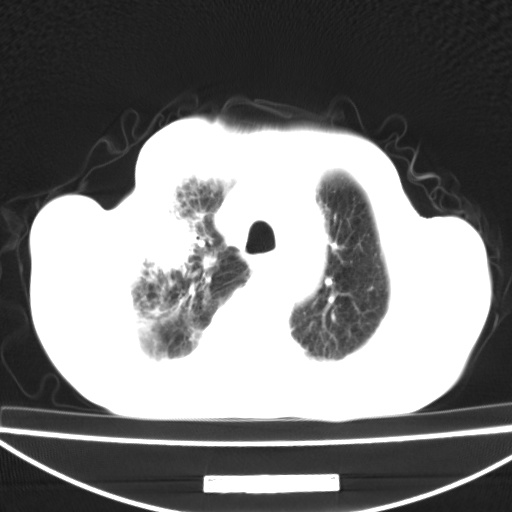

标题: CT13796:请会诊右上费病变!

患者男80岁,反复咳嗽多年,咳喘伴咯血1月

右上肺周围型肺癌伴肺门淋巴结转移.右上肺继发型肺结核.

右上肺周围型肺癌伴肺门淋巴结转移

右肺上叶占位性病变,考虑周围型肺癌,肺门淋巴结转移。要是能提供更多的临床资料就好了,以供鉴别诊断。

右肺尖周围型肺癌伴肺门淋巴结肿大

右肺上叶占位性病变,考虑周围型肺癌,肺门淋巴结转移。

右上肺周围型肺癌伴肺门、纵膈淋巴结转移

考虑为:右肺上叶肺癌伴阻塞性肺炎、右肺门及纵膈淋巴结转移。

右上肺结核合并右上肺癌,肺门淋巴结肿大